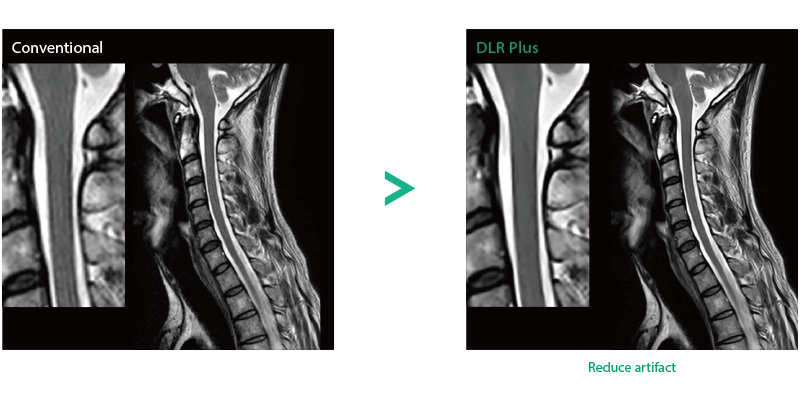

"DLR" is applicable to all body parts and promotes high speed imaging and diagnostic efficiency

IP-RAPID x DLR Plus can also shorten imaging time, allowing more images to be taken in the same examination time.

Additional imaging, such as different image types and cross sections, can be added to the conventional examination to increase the amount of information and make the diagnosis more reliable.

Deep Learning technology*8 enables image quality adjustment after imaging is complete. It optimize SNR and improve image sharpness by processing MRI signals in stages (k-space signal processing). This brings super-resolution and reduces truncation artifacts.